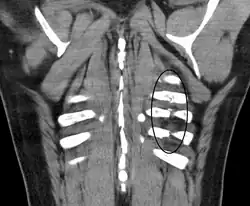

![]() Radiografía de tórax en la que son visibles varias fracturas costales señaladas por un óvalo en el hemitórax izquierdo. | ||

El diagnóstico se basa en la sintomatología y la exploración del paciente que detecta una serie de signos específicos. Las pruebas complementarias más utilizadas para confirmar el diagnóstico son la radiografía de tórax y la tomografía axial computarizada en caso de traumatismos graves.[2]